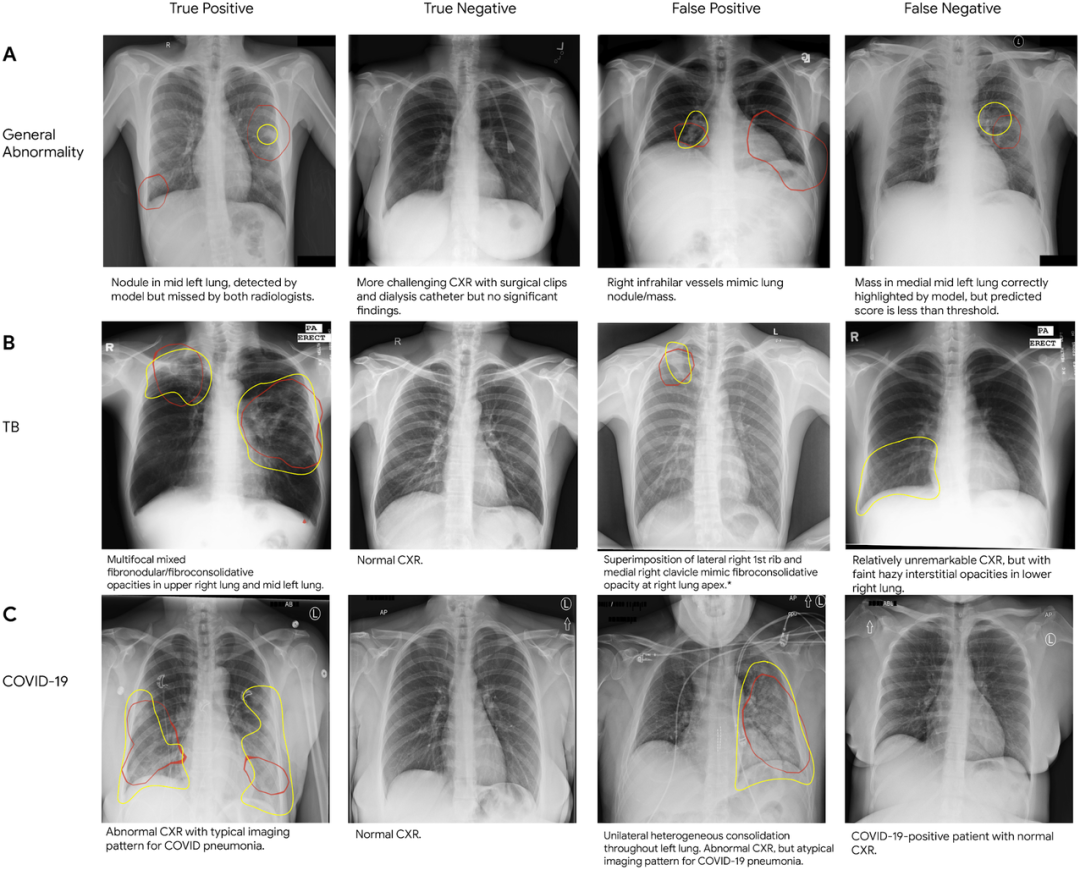

我们希望看到更多机器学习辅助系统的部署,以应用到改善乳腺癌筛查、检测肺癌、加速癌症放射治疗、标记异常x光和对前列腺癌活检分级上。机器学习为每个领域都提供了新的帮助。比如机器学习辅助的结肠镜检查,就是一个超越了原有基础的例子。结肠镜检查不仅仅只是诊断结肠癌,还可以在手术过程中切除息肉,是阻止疾病发展和预防严重疾病的前沿阵地。在该领域中,我们已经证明机器学习可以帮助确保医生不遗漏息肉,帮助检测难以发现的息肉,还可以增加维度来提高准确度,例如应用同步定位和绘图技术。在与耶路撒冷 Shaare Zedek Medical Center 医疗中心的合作中,实验证明这些系统可以实时工作,平均每次手术可以检测到一个可能会漏检的息肉,而且每次手术的错误警报少于 4 次。

图丨对(A)一般异常、(B)结核病和(C)COVID-19 的真阳性、假阳性以及真阴性、假阴性的胸部 X 光片(CXR)进行采样。在每张 CXR 中,红色的轮廓表示模型识别时关注的区域(即类激活图),黄色的轮廓表示由放射科医生认定的感兴趣区域。